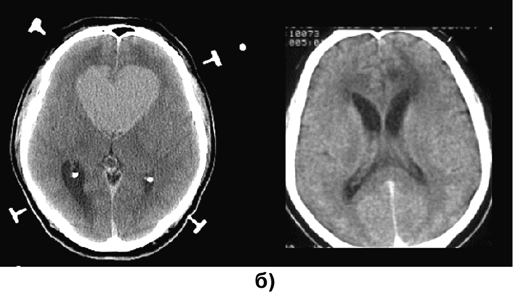

На МРТ или КТ (рис. 1) первичные лимфомы головного мозга в основном выглядят как объемные сóлидные образования гомогенно повышенной плотности, реже выявляются гипо— или изоденсные очаги. Больше 90% лимфом накапливают контраст, при этом гомогенное накопление контраста наиболее типично. Реже контрастное усиление происходит по периферии новообразования в виде кольца или не происходит вообще. В 10–30% случаев выявляется множественное поражение. Опухоли чаще располагаются супратенториально (лобные доли, подкорковые узлы, мозолистое тело, перивентрикулярно); субтенториальное распространение отмечается приблизительно в 25%, в основном в мозжечке; ствол мозга и спинной мозг поражаются редко. Первичные лимфомы ЦНС обычно локализуются в паренхиме мозга в отличие от системных лимфом («вторичное» поражение), при которых имеется лептоменингиальное распространение.

Рисунок 1. Первичные лимфомы ЦНС:

а — множественная первичная лимфома головного мозга (МРТ, Т1-взвешенные изображения с контрастным усилением, аксиальная проекция); б — лимфома медиальных отделов лобных долей, с обеих сторон распространяющаяся на колено мозолистого тела (до и через 1 год после стереотаксической биопсии и комбинированного лечения) (КТ с контрастным усилением, аксиальная проекция)

Предположение о первичной лимфоме ЦНС должно возникать всякий раз, когда на КТ обнаруживается гомогенное объемное образование повышенной плотности, особенно расположенное паравентрикулярно или вблизи от мозолистого тела и других срединных структур. Обнаружение двусторонних симметричных субэпендимарных очагов повышенной плотности подтверждает диагноз первичной лимфомы ЦНС. Перитуморозный отек, как правило, выражен меньше, чем при злокачественных глиомах и метастазах. Применение стероидов обычно приводит к существенному уменьшению и даже к исчезновению лимфом, по данным КТ или МРТ.